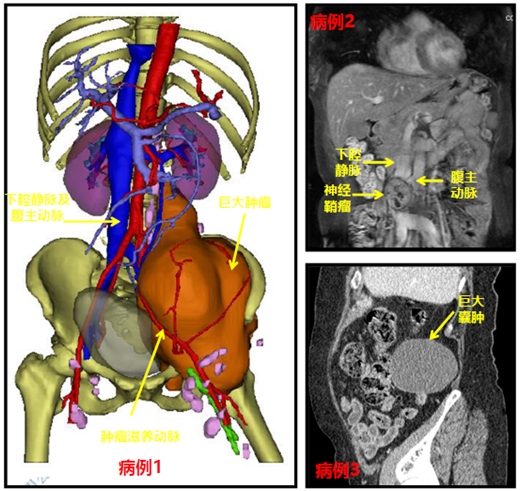

第一例患者肿瘤巨大,CT显示最大直径为237mm,肿瘤侵犯破坏髂骨、髋臼并包绕髂动脉,左髂静脉受压完全闭塞合并下肢深静脉血栓形成,左下肢及左上肢严重肿胀,唐博副教授及罗海龙主治医师、颜海燕住院医师、张灏龙住院医师团队针对该患者先行上腔静脉及下腔静脉滤器置入术,后腹膜肿瘤滋养动脉栓塞术,尽可能减少血栓脱离导致肺栓塞风险及肿瘤切除术时大出血风险,介入后12小时内在全麻下行后腹膜巨大恶性肿瘤切除术,术中出血少于200ml,手术非常顺利,术后患者左下肢肿胀明显缓解,患者及其家属十分感激。第二例患者秀山患者,罗文军教授及唐博副教授团队采用经后腹膜入路紧贴下腔静脉及腹主动脉行神经鞘膜瘤完整切除术,手术时间仅不到2小时,术后第2天患者下床活动,患者及其家属非常满意。第三例患者BMI大于30,且有2型糖尿病,考虑肿瘤良性可能性较大,唐博副教授团队充分评估其伤口感染风险后,为减少腹腔脏器损伤风险,最终选择全腹腔镜下经后腹膜入路行后腹膜巨大肿瘤切除术(术中冰冻提示为中肾来源腹膜囊肿),手术完整切除囊肿,术中出血仅30ml左右,术后患者第2天自己下床活动,自诉完全无疼痛感,术后第4天出院。

原发性腹膜后肿瘤(PRT)发病率低,占全身肿瘤的0.07%~0.2%、软组织肿瘤的10%~20%,其中80%为恶性,以恶性淋巴瘤和脂肪肉瘤为主,20%的良性肿瘤则以神经纤维瘤为主。腹膜后肿瘤因位置隐蔽,症状较晚才出现,发现时一般体积较大,易压迫或侵犯大血管和周围器官。PRT应尽可能手术完全切除,如有血管受累,应行血管重建,这对提高治愈率和延长患者的生存期极为有利。此类手术往往手术难度大,其原因一般有以下两点:第一PRT位置深、体积大、显露困难,特别是肿瘤位于盆腔者,显露更加困难,使切除难度增加;第二PRT多与腹膜后重要脏器及大血管粘连,术中易造成难以控制的大出血。选择开放手术还是腔镜手术尚无统一标准。开放手术虽然创伤大,但是在血管重建、器官修复方面明显优于腹腔镜。腹腔镜手术创伤小,与重要脏器或大血管粘连不紧密的囊性或体积较小的腹膜后肿瘤,以探查为目的腹腔镜切除手术切实可行。良好的手术效果依赖于术者对病例的准确分析及术者自身的临床经验以及充分的术前准备及多学科协助。